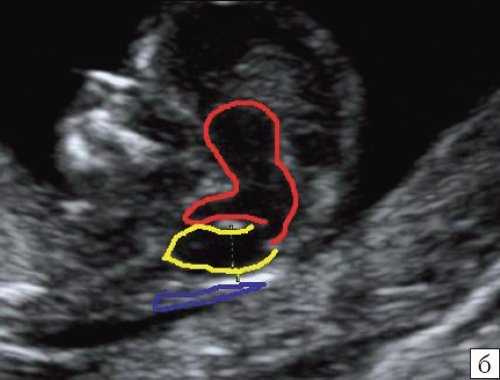

б) Вид "осьминожки":

- красный цвет - диэнцефалон (таламус), со стволом мозга (верхняя ножка) и IV желудочком (нижняя ножка);

- желтый цвет - большая цистерна головного мозга;

- синий цвет - воротниковое пространство.

Новый ультразвуковой маркер в изучении нормальной ультразвуковой анатомии головного мозга плода в срок 11-14 недель беременности

Особенности визуализации изложенных выше структур в данном сроке позволили нам выделить и назвать новый ультразвуковой маркер нормальной ультразвуковой анатомии мозга плода. Структуры головного мозга плода в этой области схожи с осьминогом, у которого есть голова и две приблизительно равновеликие по диаметру ножки, представляющие собой ствол мозга и IV желудочек. Ниже ножек "осьминожки" визуализируется 2 "подушки осьминожки" - это два анэхогенных пространства - большая цистерна и воротниковое пространство (рис. 2, б).

Так как речь идет о сроках первого скрининга, т.е. раннего осмотра, новый ультразвуковой маркер мы назвали "осьминожкой" (рис. 3).

а) Стрелками указана голова "осьминожки" - диэнцефалон (таламус).

б) Красный цвет - диэнцефалон (таламус), со стволом мозга (верхняя ножка) и IV желудочком (нижняя ножка); желтый цвет - большая цистерна головного мозга; синий цвет - воротниковое пространство.

Как сказано выше, имеет значение и измерение ножек "осьминожки", так среднее значение диаметра нижней ножки, т.е. IV желудочка в зависимости от КТР в срок 11-14 недель варьирует от 1,5 до 2,5 мм (рис. 4).